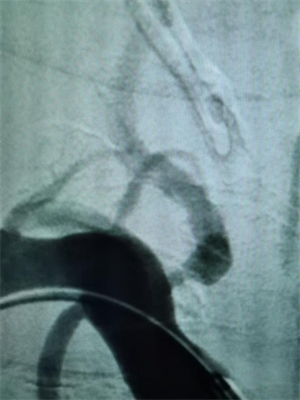

△图一:手术前可见后交通动脉瘤合并多个突起

△图二:手术后动脉瘤已经栓塞,造影不可见